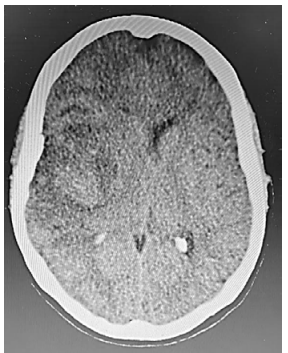

Um paciente do sexo masculino, com 47 anos, é levado pela família ao pronto atendimento com dificuldade de movimentação do dimidio esquerdo, progressiva, há quatro semanas. No dia anterior, apresentou cefaleia holocraniana que piora quando se deita, quando tosse, ou com qualquer esforço, provocando vômitos. Ao exame: escala de coma de Glasgow (ECG) 14 (M6V5O3), pupilas isocóricas e fotorreagentes. Hemiparesia esquerda grau 4 (MRC), proporcionada e completa, com sinais de liberação piramidal. Realizou tomografia de crânio conforme figura 1 abaixo. Após a realização do exame de imagem o paciente rebaixou o nível de consciência para ECG 8. Um novo exame de fundo de olho demonstrou papiledema.

Elaborado pelo(a) autor(a).

Frente a evolução clínica do paciente, as medidas clínicas padronizadas a serem realizadas emergencialmente incluem, além da entubação orotraqueal para a proteção de via aérea,